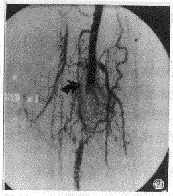

图2 显示患者股浅动脉血栓栓塞,血管中断(箭头所示),远端血管经侧支循环显影。

图3 与图2同一病人,经ATD三个来回切割,示股浅动脉通畅恢复血流。

Amplatz血栓切割器是一种机械血栓切割器。从设计理论上,Amplatz血栓切割器是一种高效可循环切栓器。本组实验对重量6±0.5g,大小1cm×6cm血凝块采用转速80000rpm,100000rpm和120000rpm,时间仅30s进行切割。结果切碎颗粒小于15μm占总重量分别为94.%,96.19%和94.7%。在临床应用中,采用转速100000rpm,时间32~330s,平均时间为165s,完全切除成功率80%(图2、3)。由此可见此法对急性或亚急性血栓能快速、省时、有效。但对血栓切割器切碎的血栓颗粒是否会引起远端外周血管或肺血管栓塞临床更为关注。Yasui等[2] 报道Amplatz血栓切割器切割后的血栓颗粒无大于1000μm,且对4d和10d血栓切割后,小于13μm血栓颗粒占总重量分别为99.2%和98.8%。本实验结果显示与此类似。在临床应用中,Coleman等[3]报道和本组结果均无远端血管或肺血管栓塞发生。尤其近来应用Amplatz血栓切割器成功地治疗急性肺动脉血栓(图4、5), 故认为此法安全可行。